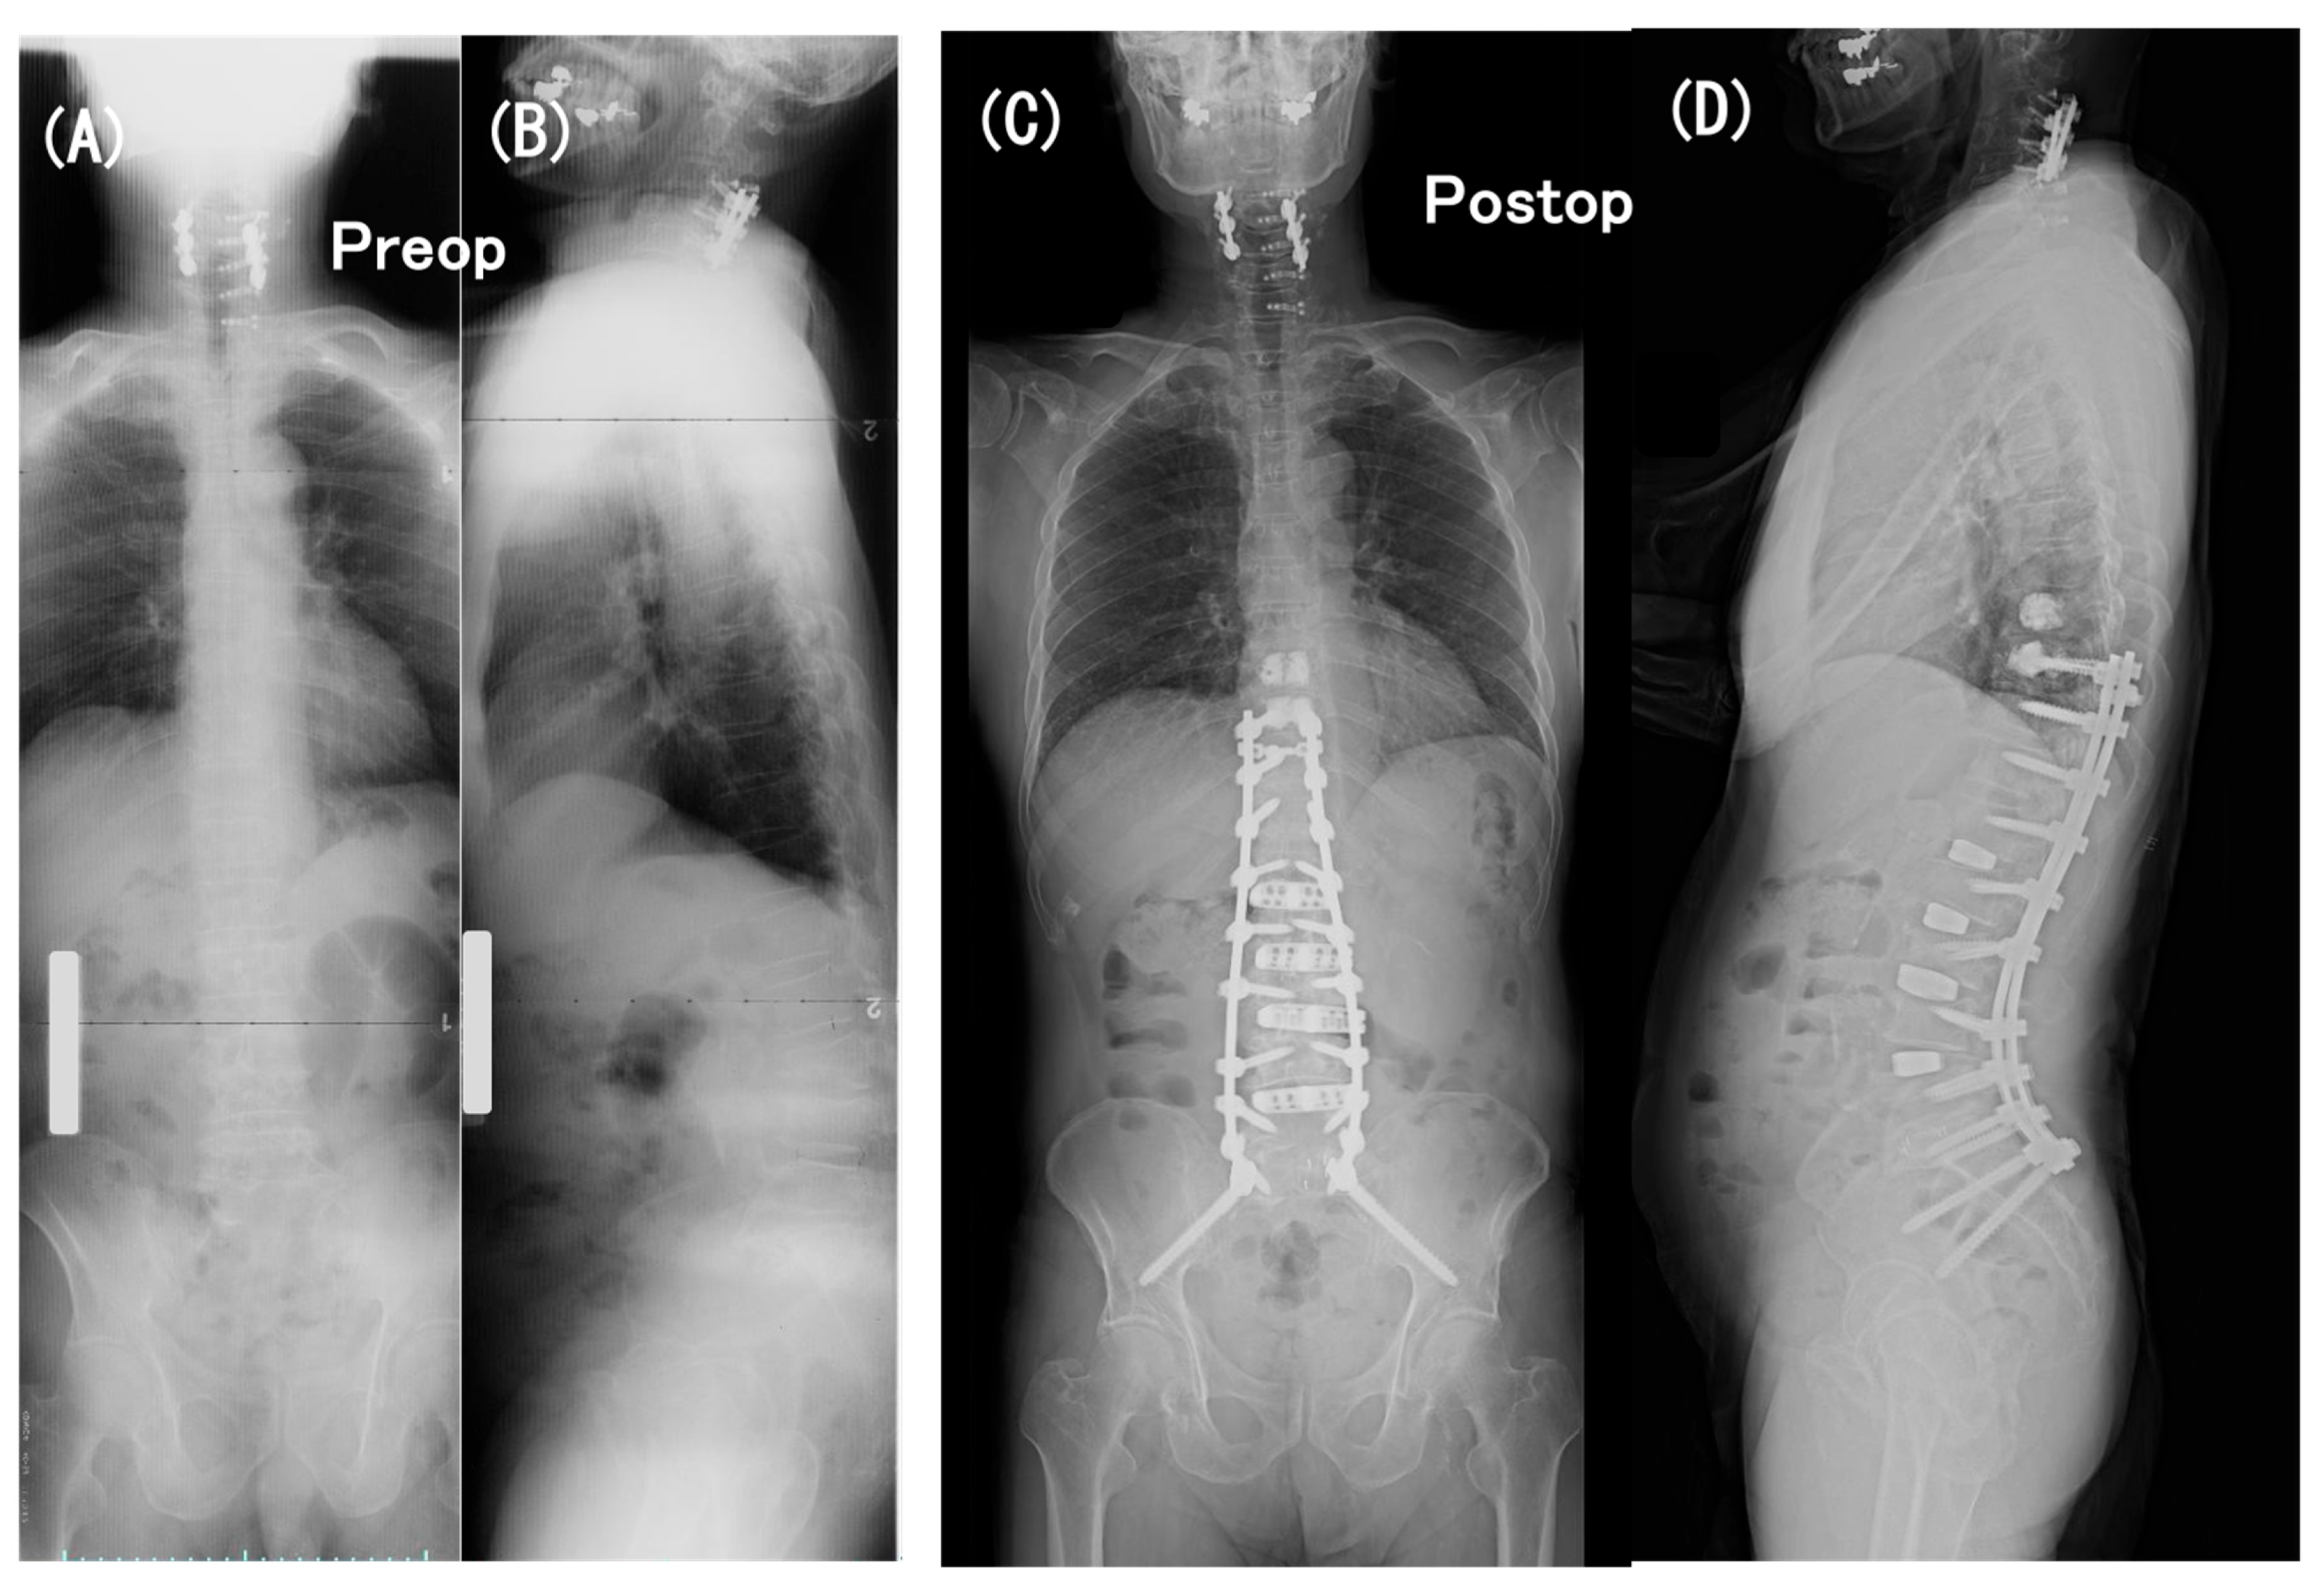

3.6. Case Presentation

- Case no. 6

- 2.

- Case no. 4